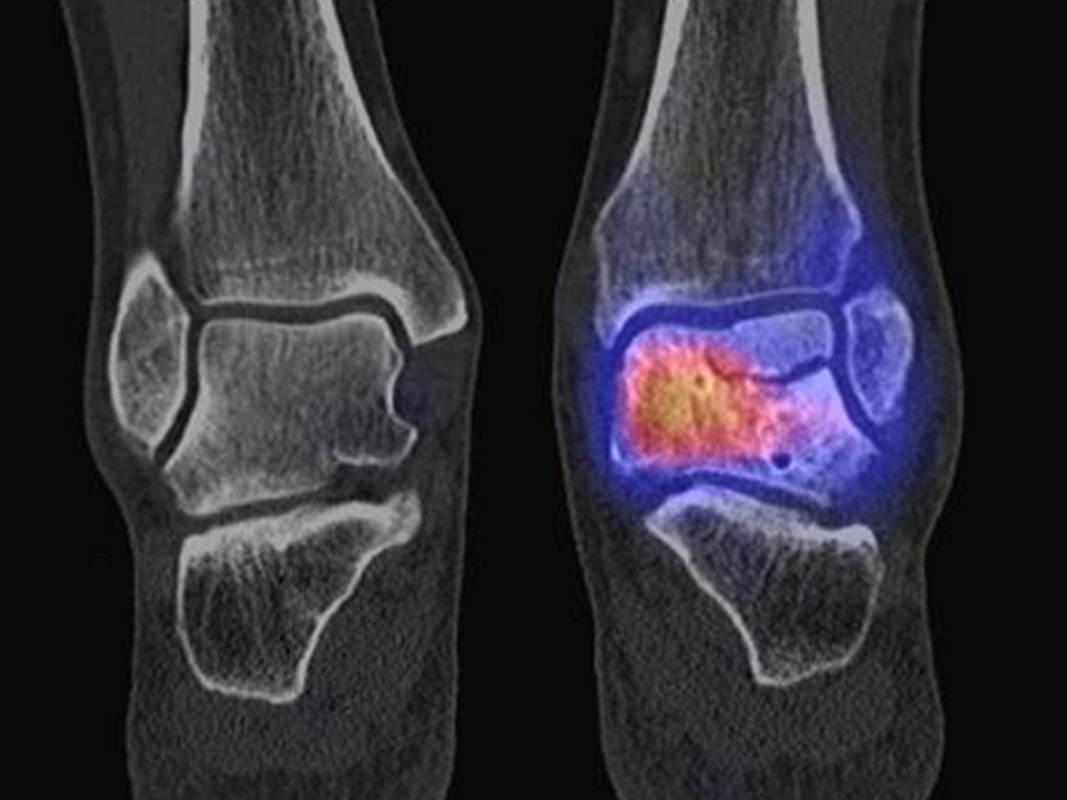

Osteonekrosen

Abbildung 9.2.a bis d: SPECT/CT zur Beurteilung der Knochen-Vitalität bei einer Talusnekrose. 5 Jahre zuvor während der Arbeit war die Patientin beim Treppensteigen umgeknickt und zog sich Außenbandrupturen zu. Nachfolgend persistierende Beschwerden mit Entwicklung einer Talusnekrose. Frage nach Vitalität und Ausdehnung der Nekrose. Deutliche bis intensive Traceranreicherung im Bereich des linken Talus. Im SPECT/CT befindet sich der Hypermetabolismus in allen Abschnitten des Talus mit relativer Aussparung eines sich demarkierenden Fragmentes lateral, was die laterale Talusschulter umfasst, die Größe beträgt transversal ca. 23 x 16 mm. In diesem Fragment relativ homogene Skelettstruktur, diese Befunde weisen auf eine trophische bzw. nekrotische Störung des Talus hin mit einem sich demarkierendem Fragment, welches die laterale Talusschulter beinhaltet.

Die Abbildung 9.3.a bis d zeigt ein weiteren Fall mit einer SPECT/CT zur Beurteilung der Knochen-Vitalität bei einer Talusnekrose. Die Bilder zeigen eine abgelaufene Nekrose mit zystischen Resorptionen des linken Talusdoms bei nachweislich erhaltener Vitalität der umgebenden Knochenabschnitte aufgrund des hier überall deutlich erhöhten Knochenmetabolismus (= inkomplette Restitutio). Aufgrund der nachweislich erhaltenen Vitalität konnte erfolgreich eine Knochen-Transplantation erfolgen.Deutlich geringer ausgeprägte nekrotische Veränderungen auch im rechten Talusdom bei hier weitgehend erhaltenen Gelenkkonturen.